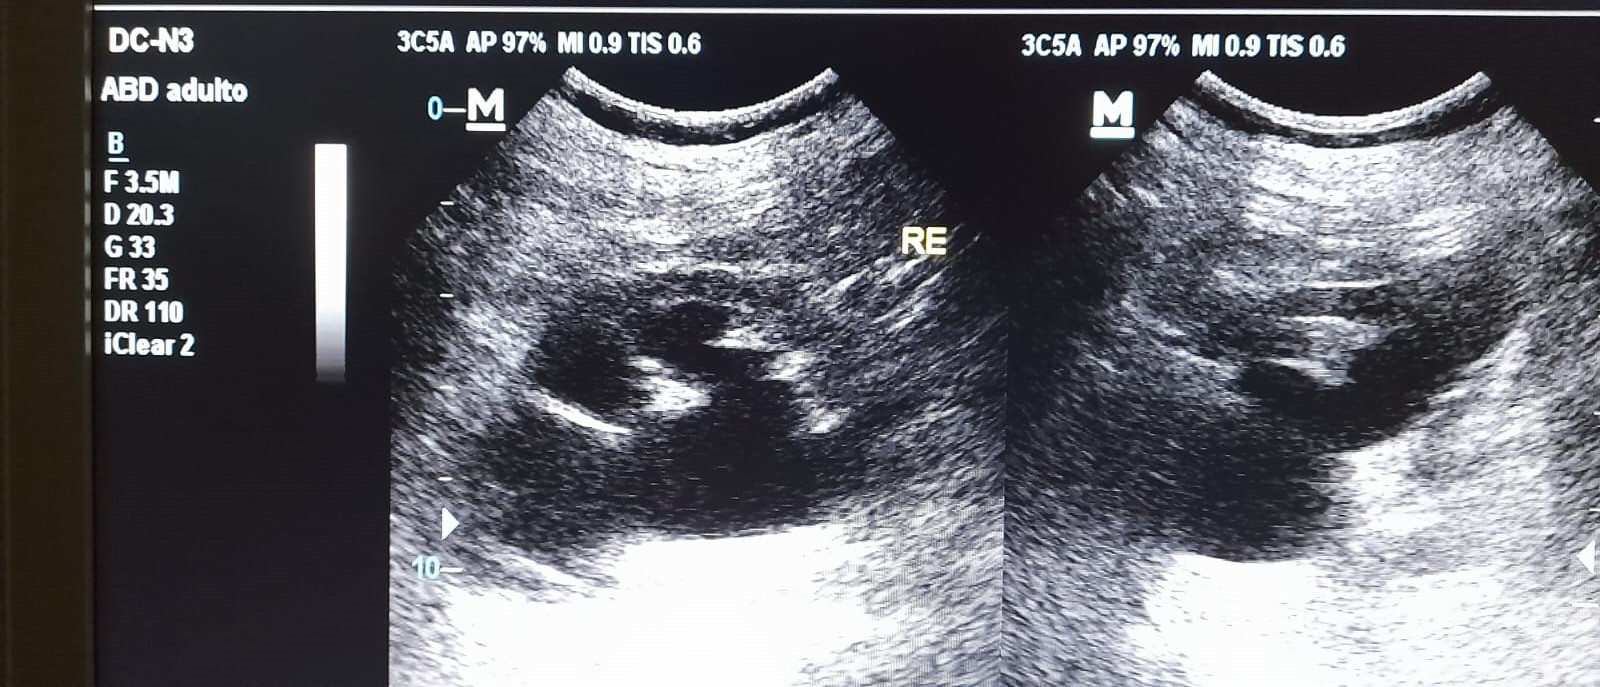

En la ecografía realizada en el ambulatorio observamos una hidronefrosis renal izquierda con líquido libre peritoneal y derivamos a urgencias de urología para estudio y manejo.